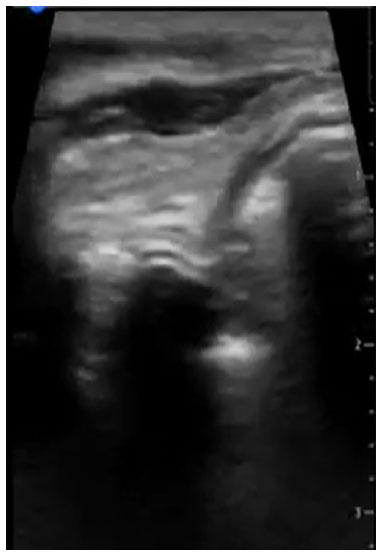

A imagem única da interface ar-mucosa, correspondendo a traqueia, deve ser visualizada para confirmar que não há tubo posicionado no esôfago do paciente. Esse artefato de reverberação posterior da imagem traqueal é também chamado de rabo de cometa, como mostra a Figura 1. Caso haja intubação esofágica, o canal anteriormente fechado (Figura 2), passa a estar aberto com o tubo em seu interior, onde visualizamos dois artefatos de rabo de cometa, com duas interfaces ar-mucosa com sombra posterior, visualizado na posição póstero-lateral a traqueia, como mostra a Figura 3.